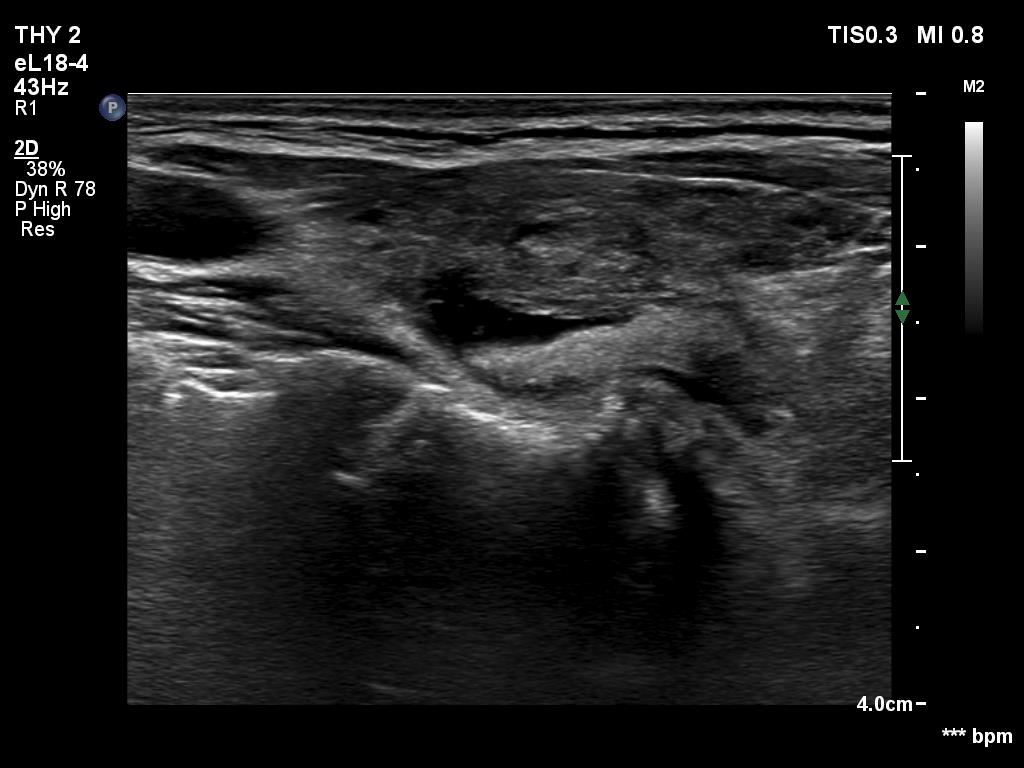

Ultrasonography. The thyroid was hypoechoic and presented several more hypoechoic and echonormal islets corresponding to the underlying thyroiditis. There was a mixed, dominantly cystic mass dorsal to the lower two-third of the right lobe. The lesion has echonormal solid part and showed intracystic echogenic figures.